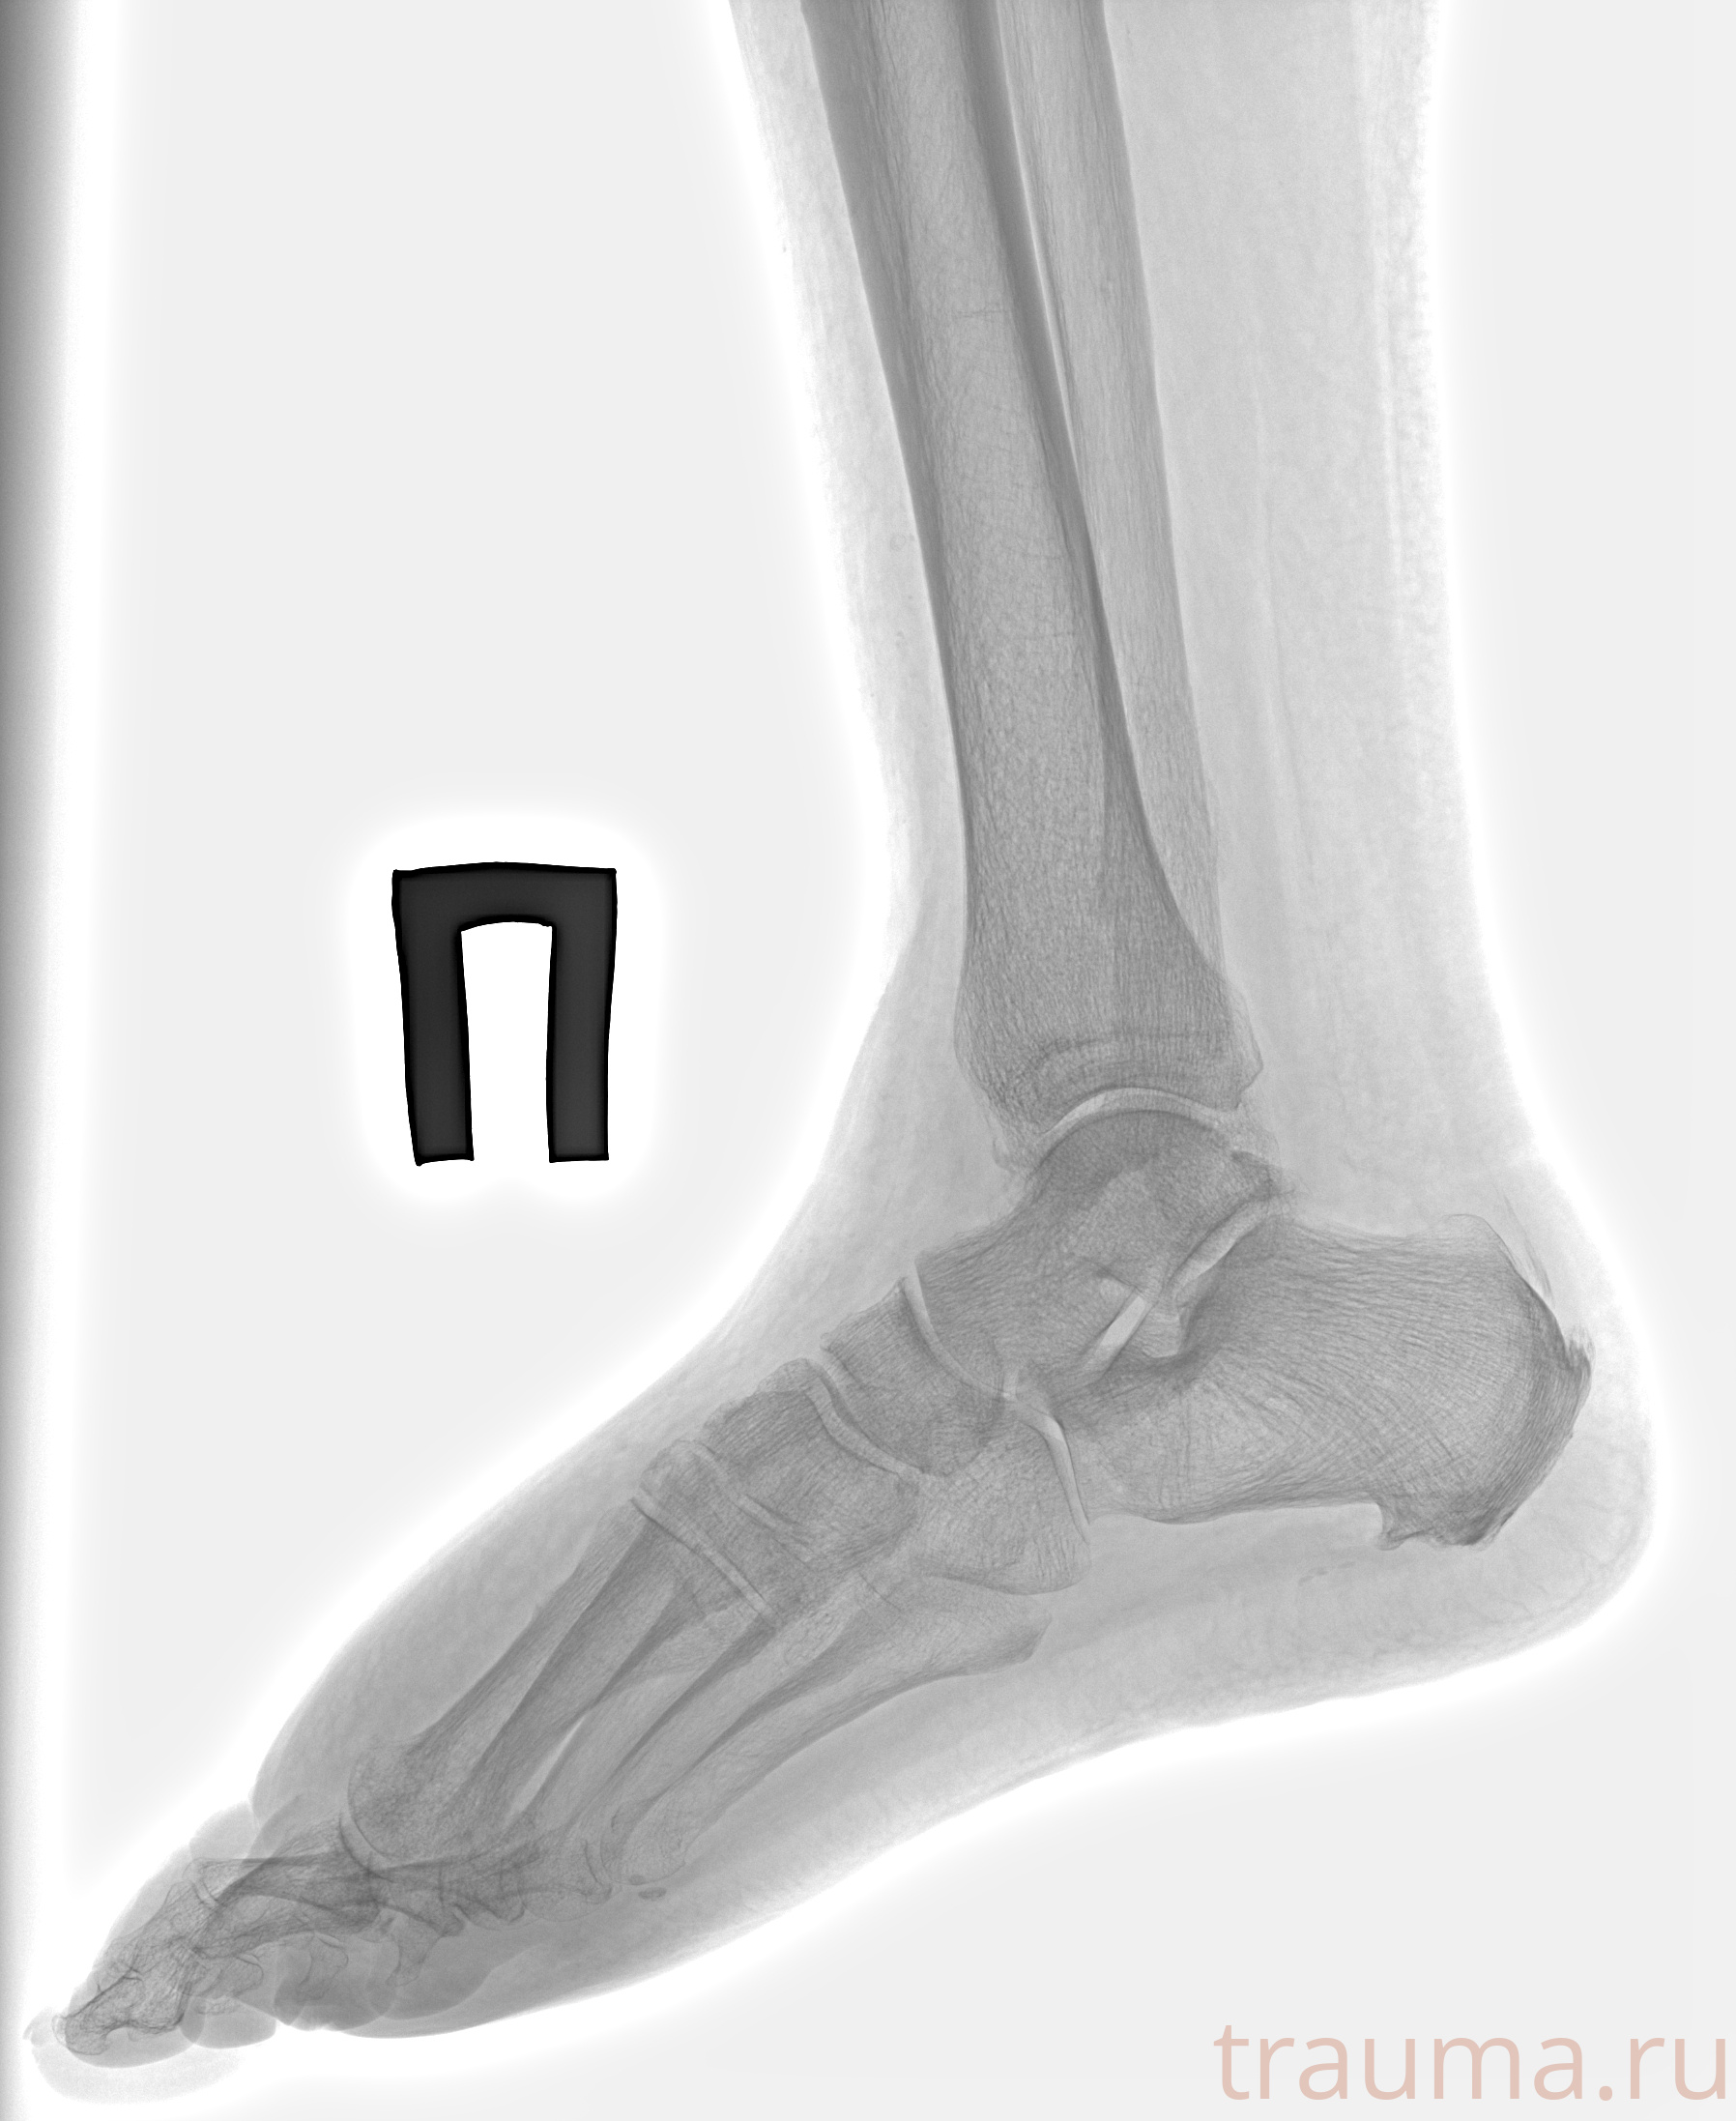

Рентген на дому: по вашему адресу приезжает врач-рентгенолог, травматолог-ортопед с мобильным рентгеновским аппаратом, проводит диагностику травмы или заболевания, делает необходимые рентгенограммы, дает рекомендации по дальнейшему лечению. Получить качественные снимки в домашних условиях возможно благодаря уникальной методике, разработанной МосРентген Центром для института  Склифосовского